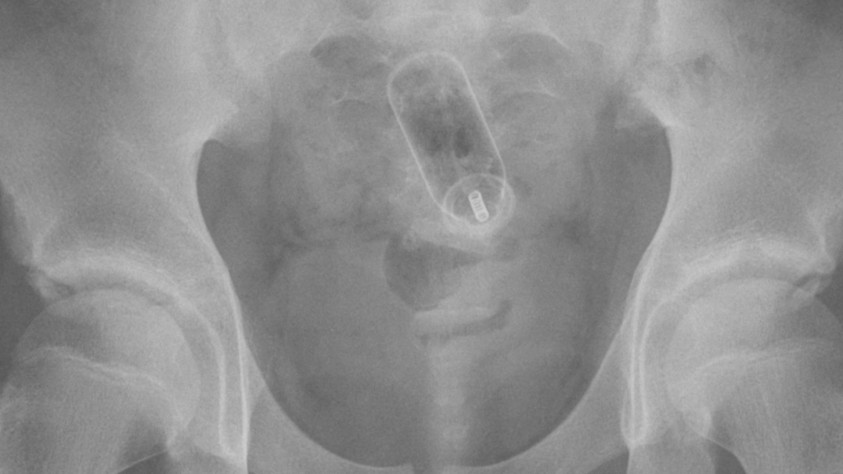

Примерно в конце 2023 года был зафиксирован первый случай подобного «читерства», правда, не в киберспорте, а в шахматах.

Блогеры сумели обыграть гроссмейстера, используя весьма нестандартный способ передачи подсказок: секс игрушку в анусе, которой удалённо управляли и с помощью вибраций передавали подсказки по ходам.